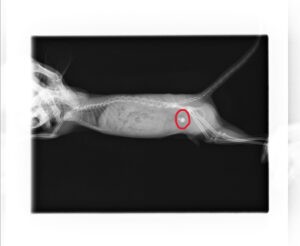

【診断】

診断は臨床症状と画像検査を組み合わせて行います。血尿、排尿時の疼痛、頻尿、尿量減少、食欲低下などが主な症状です。X線検査ではカルシウム含有結石が高頻度に描出され、診断に有用です。超音波検査では膀胱内の結石の位置や大きさ、膀胱壁の肥厚の有無を評価できます。必要に応じて尿検査を行い、炎症や感染の有無を確認します。